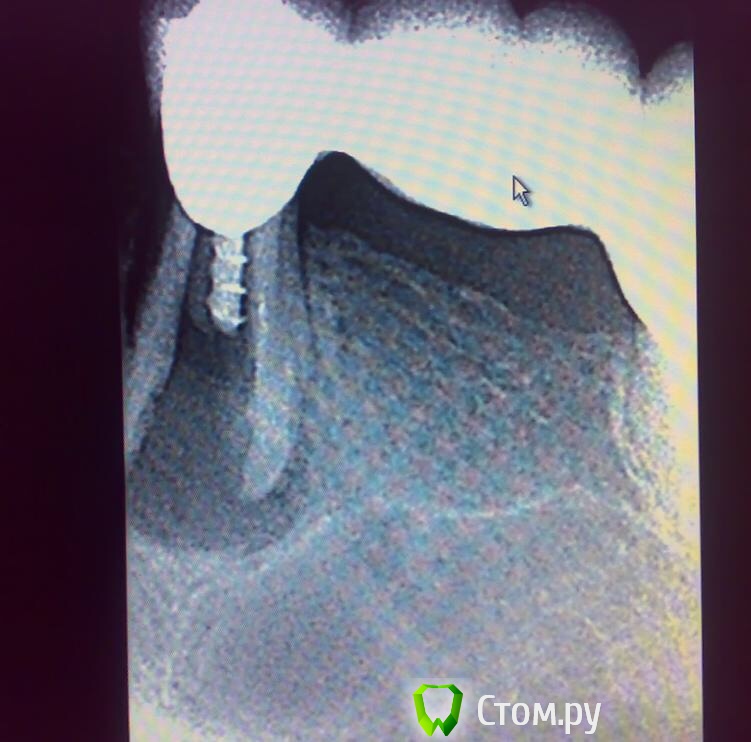

Shaid Опубликовано 3 сентября, 2014 Поделиться Опубликовано 3 сентября, 2014 Пациент не мой, объективно не могу ничего сказать. Жалобы на тяжесть и неприятные ощущения в зубе.http://s008.radikal.ru/i305/1409/d8/2d7bf5938f53.jpghttp://s001.radikal.ru/i195/1409/e7/3aa032b07d0f.jpg 1 Ссылка на комментарий

anvladd Опубликовано 3 сентября, 2014 Поделиться Опубликовано 3 сентября, 2014 похоже треснул так. 1 Ссылка на комментарий

Паращук Роман Опубликовано 3 сентября, 2014 Поделиться Опубликовано 3 сентября, 2014 Да ладно...))) Две линии перелома+карман на 2/3 длины корня и вы сомневаетесь. Имхо бюгель на аттачментах постарался. 1 Ссылка на комментарий

togrul Опубликовано 3 сентября, 2014 Поделиться Опубликовано 3 сентября, 2014 Скорее всего сломался, видна линия перелома Ссылка на комментарий

doktor vv Опубликовано 3 сентября, 2014 Поделиться Опубликовано 3 сентября, 2014 100 процентов треснулТакие вещи также наблюдал когда терапевты штифты юниметрик ставилиЧаще на премолярахЕсли тут еще и бюгель то это закономерные результат Ссылка на комментарий